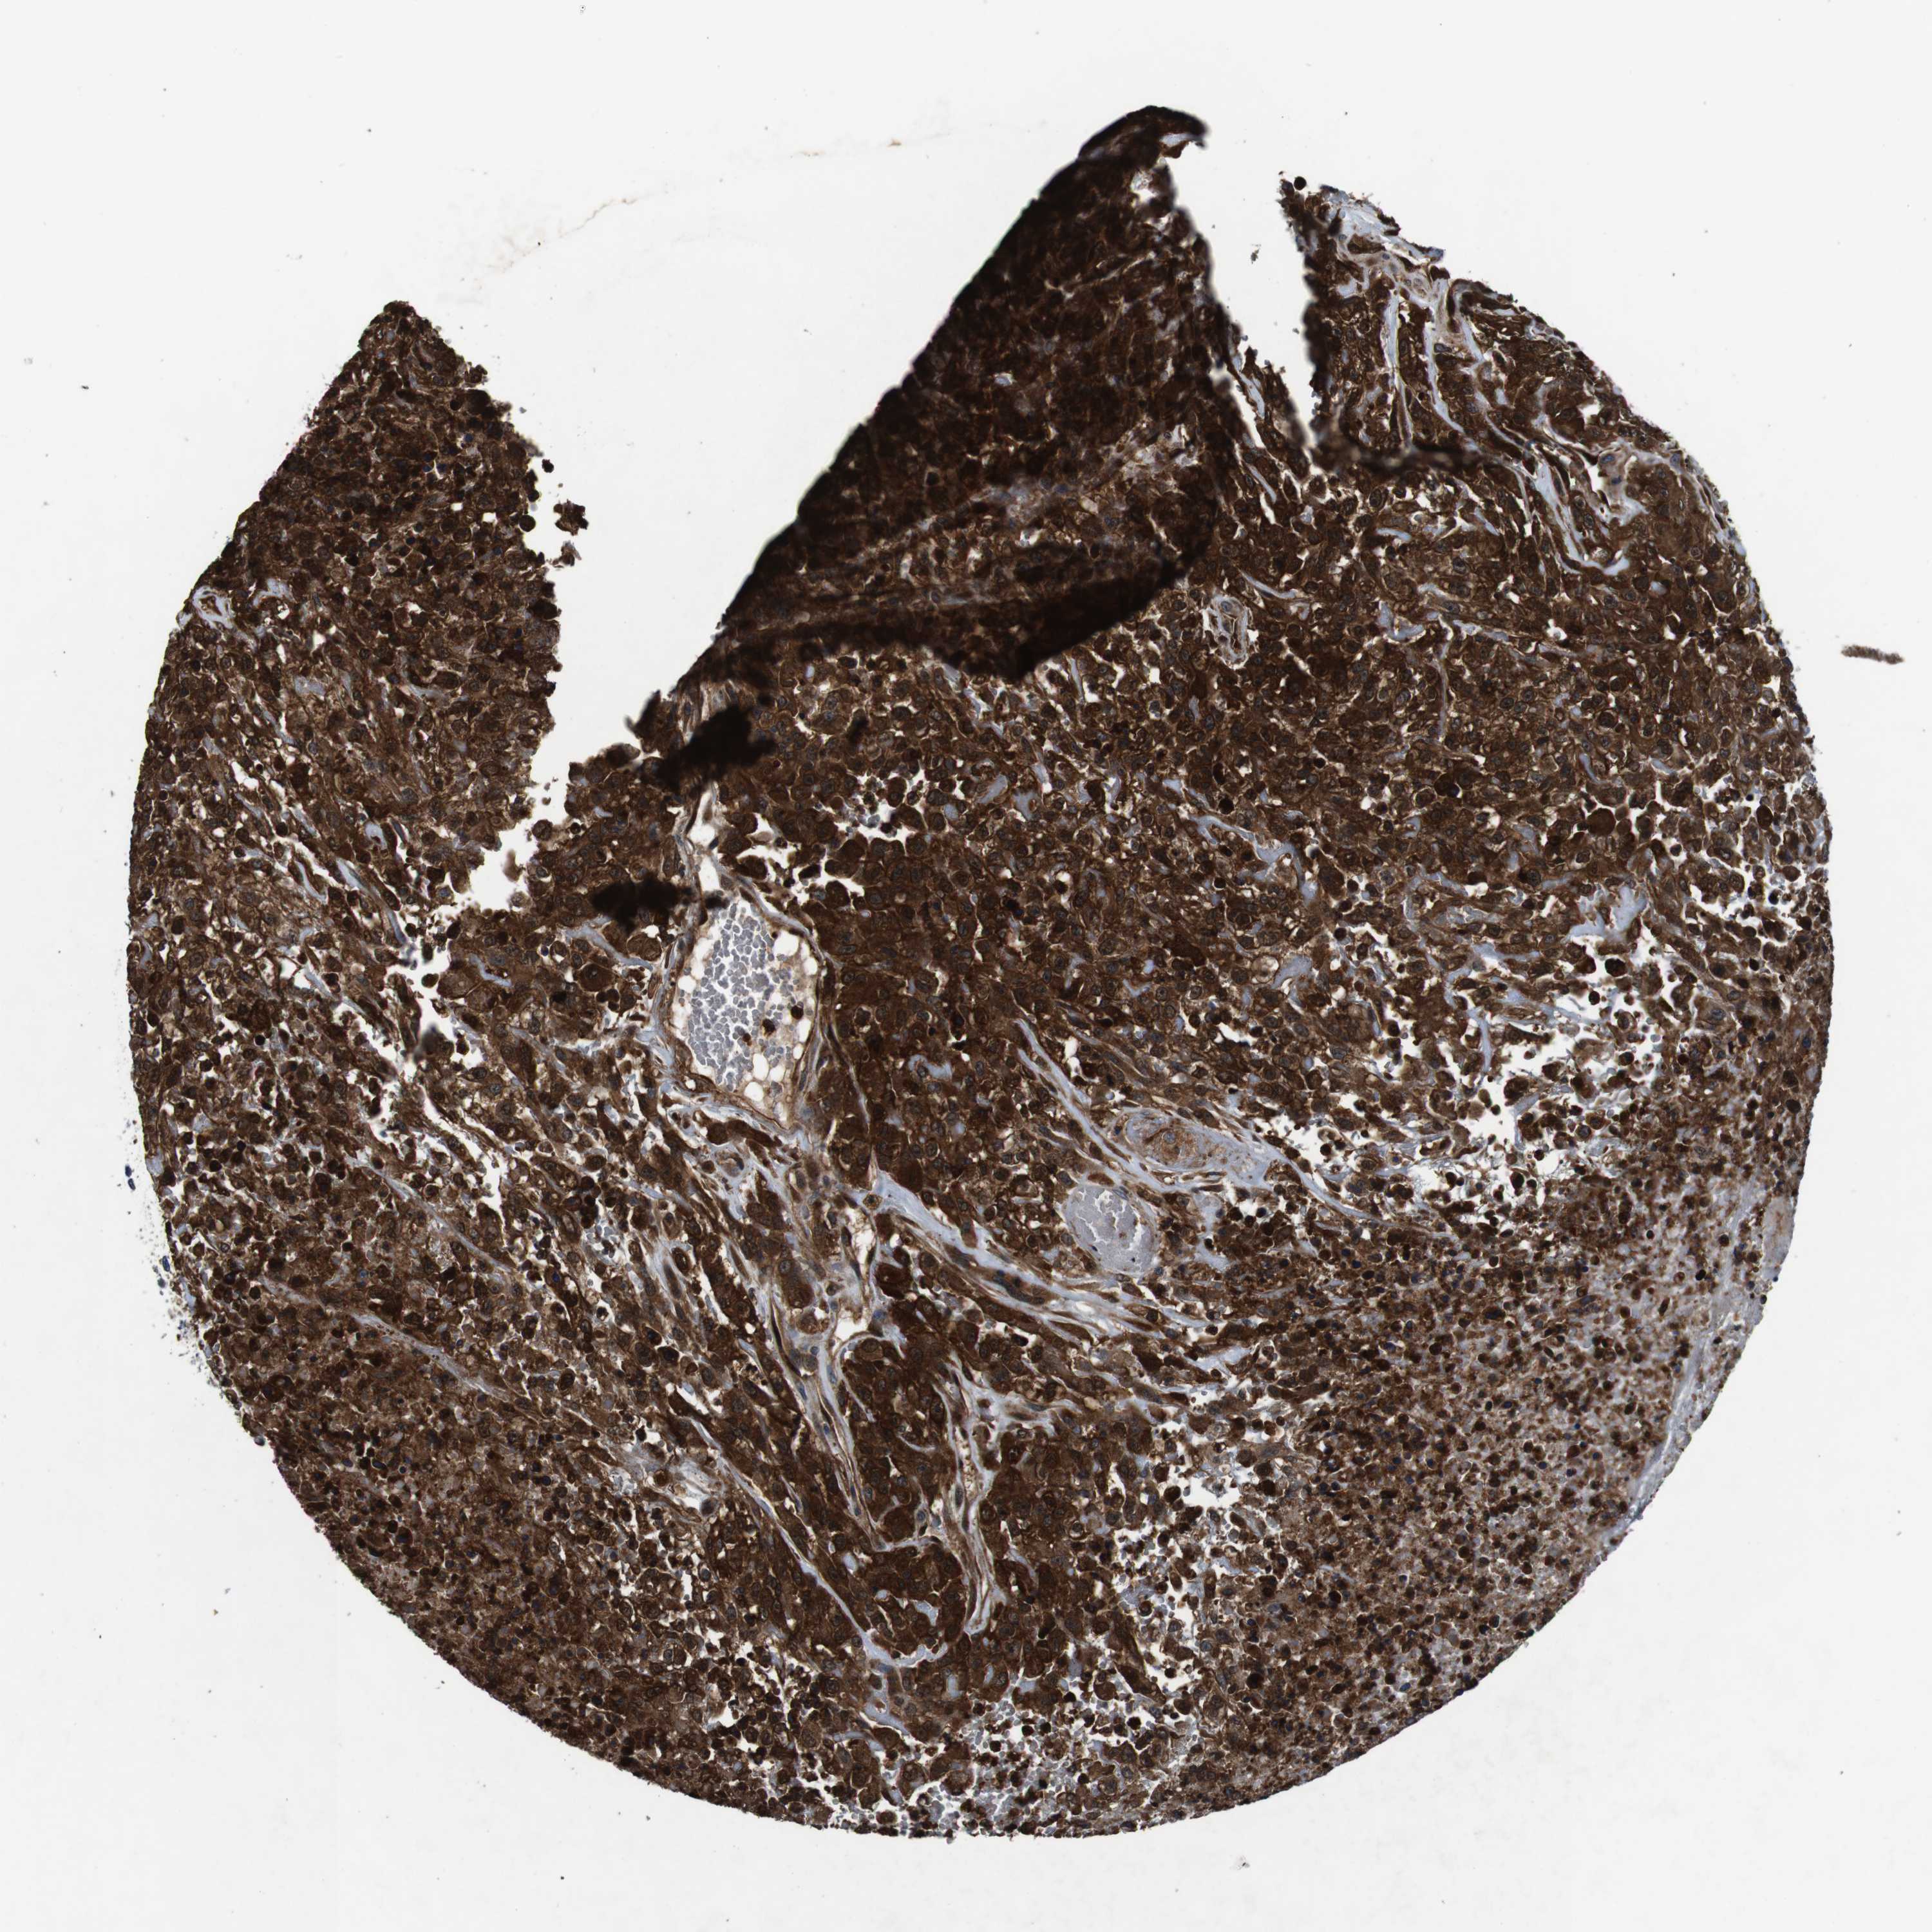

UROTHELIAL CANCER - Protein expressioni

A mouse-over function shows sample information and annotation data. Click on an image to view it in a full screen mode. Samples can be filtered based on level of antibody staining by selecting one or several of the following categories: high, medium, low and not detected. The assay and annotation is described here.

Note that samples used for immunohistochemistry by the Human Protein Atlas do not correspond to samples in the TCGA dataset.

Antibody stainingi

Antibody staining in the annotated cell types in the current human tissue is reported as not detected, low, medium, or high, based on conventional immunohistochemistry profiling in selected tissues. This score is based on the combination of the staining intensity and fraction of stained cells.

Each image is clickable and will lead to virtual microscopy that enables deeper exploration of all samples and also displays staining intensity scores, fraction scores and subcellular localization as well as patient and tissue information for each sample.

HPA011271

HPA011272

CAB013023

CAB035987

CAB058693

CAB080415

Staining

High

Medium

Low

Not detected

Intensity

Strong

Moderate

Weak

Negative

Quantity

>75%

75%-25%

<25%

None

Location

Nuclear

Cytoplasmic/membranous

Cytoplasmic/membranous,nuclear

Urothelial carcinoma, Low grade

Urothelial carcinoma, High grade

Urothelial carcinoma, NOS